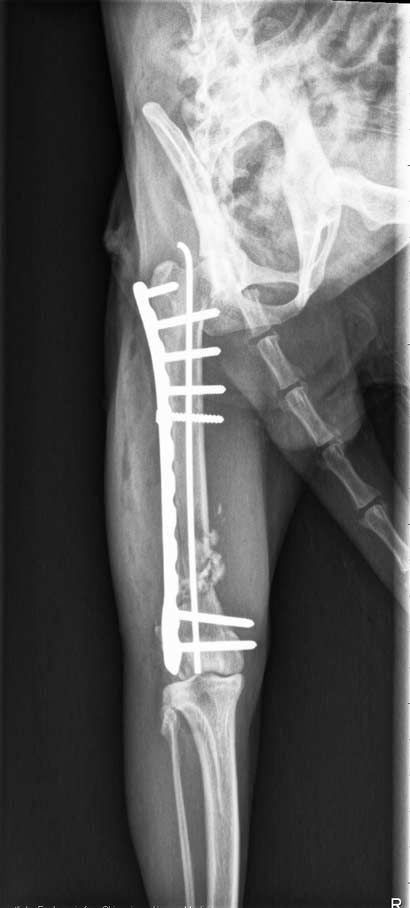

Wir brachten Jaloux in eine chirurgische Klinik, in der unser Kater gleich am nächsten Tag von einem Spezialisten operiert wurde.

Die Fraktur wurde mit einer Platten-Osteosynthese und einem Pin versorgt und der Bruch somit stabilisiert. Jaloux war sehr geschwächt und hatte einiges an Blut verloren, doch er befindet sich nun auf dem Weg der Besserung.

Bilder

post-op:

|